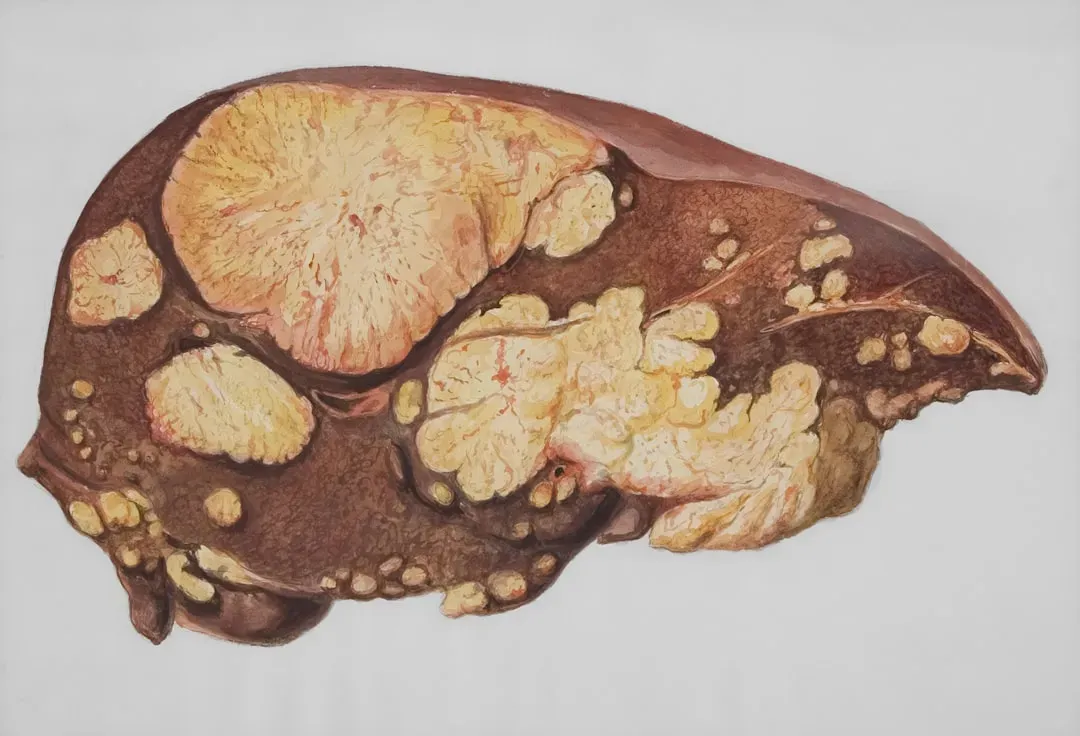

The Liver: The Quiet Regeneration Champion

If the body had a “most underrated healer” award, the liver would probably win it. This organ helps filter toxins, process nutrients, and manage an enormous number of chemical reactions that keep you alive, all while having a rare superpower: the ability to regenerate lost tissue. If part of the liver is removed or damaged, the remaining cells can grow and divide to restore overall function, as long as there’s enough healthy tissue left and the damage doesn’t keep happening.

That doesn’t mean the liver is invincible – in fact, long-term alcohol use, certain medications, and chronic infections can scar it to the point where regeneration can’t keep up. But the very fact that it can bounce back from significant injury at all is impressive. It’s a bit like having a workforce that can suddenly double its efforts when members are laid off, redistributing tasks and rebuilding capacity in ways most organs just can’t match.